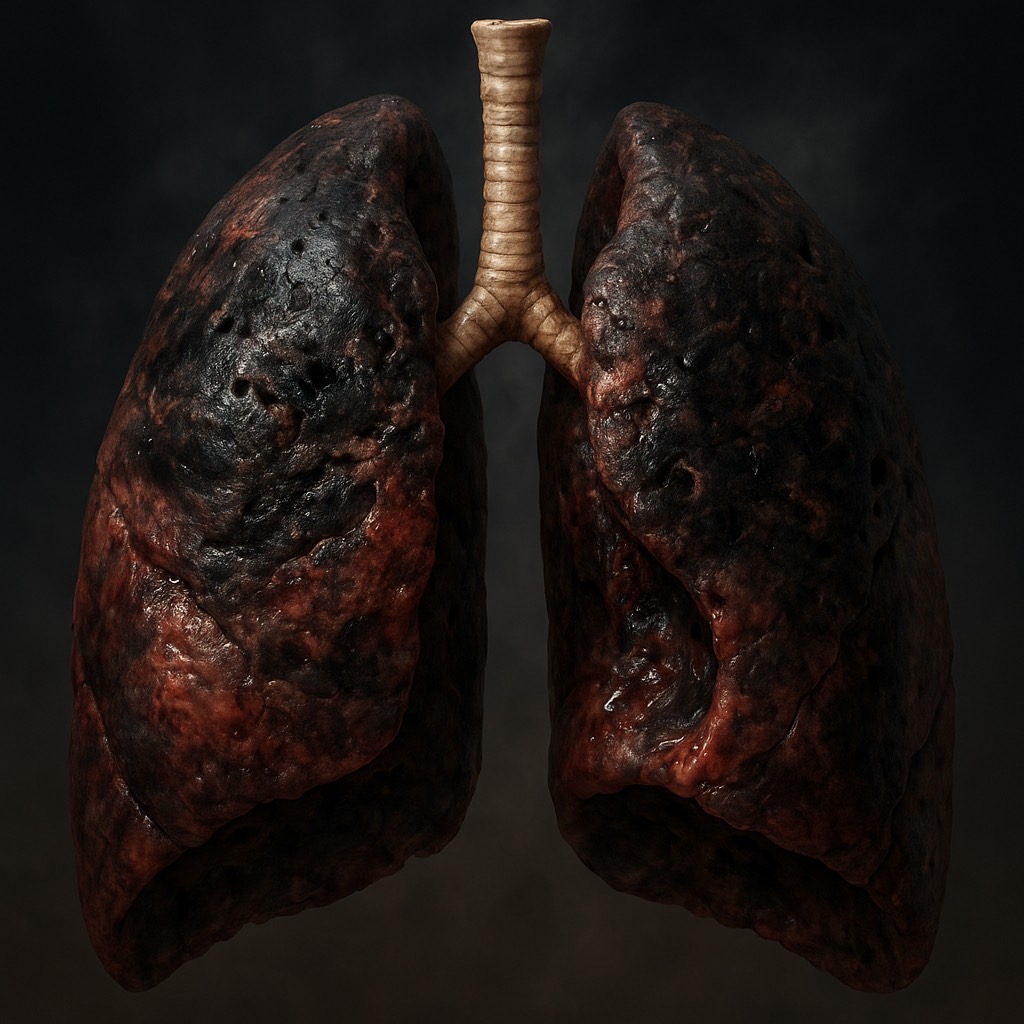

หลายคนเข้าใจว่าการไม่มีการเผาไหม้ของยาสูบทำให้บุหรี่ไฟฟ้าปลอดภัยกว่า แต่การวิจัยจำนวนมากพบว่า:

- ไอระเหยจากบุหรี่ไฟฟ้ามีสารพิษ เช่น ฟอร์มาลดีไฮด์ (formaldehyde) และ อะโครลีน (acrolein)

- ส่งผลต่อ ปอด และ หลอดเลือด

- ทำให้เกิด โรคหัวใจและหลอดเลือด